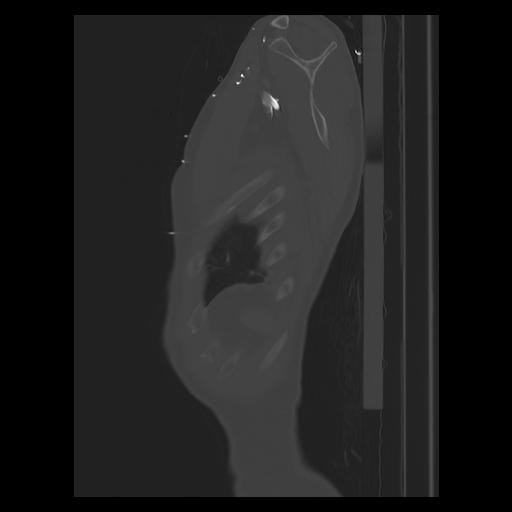

33 PULMON,CE,Sagittal,3.000,PULMON,Sagittal,